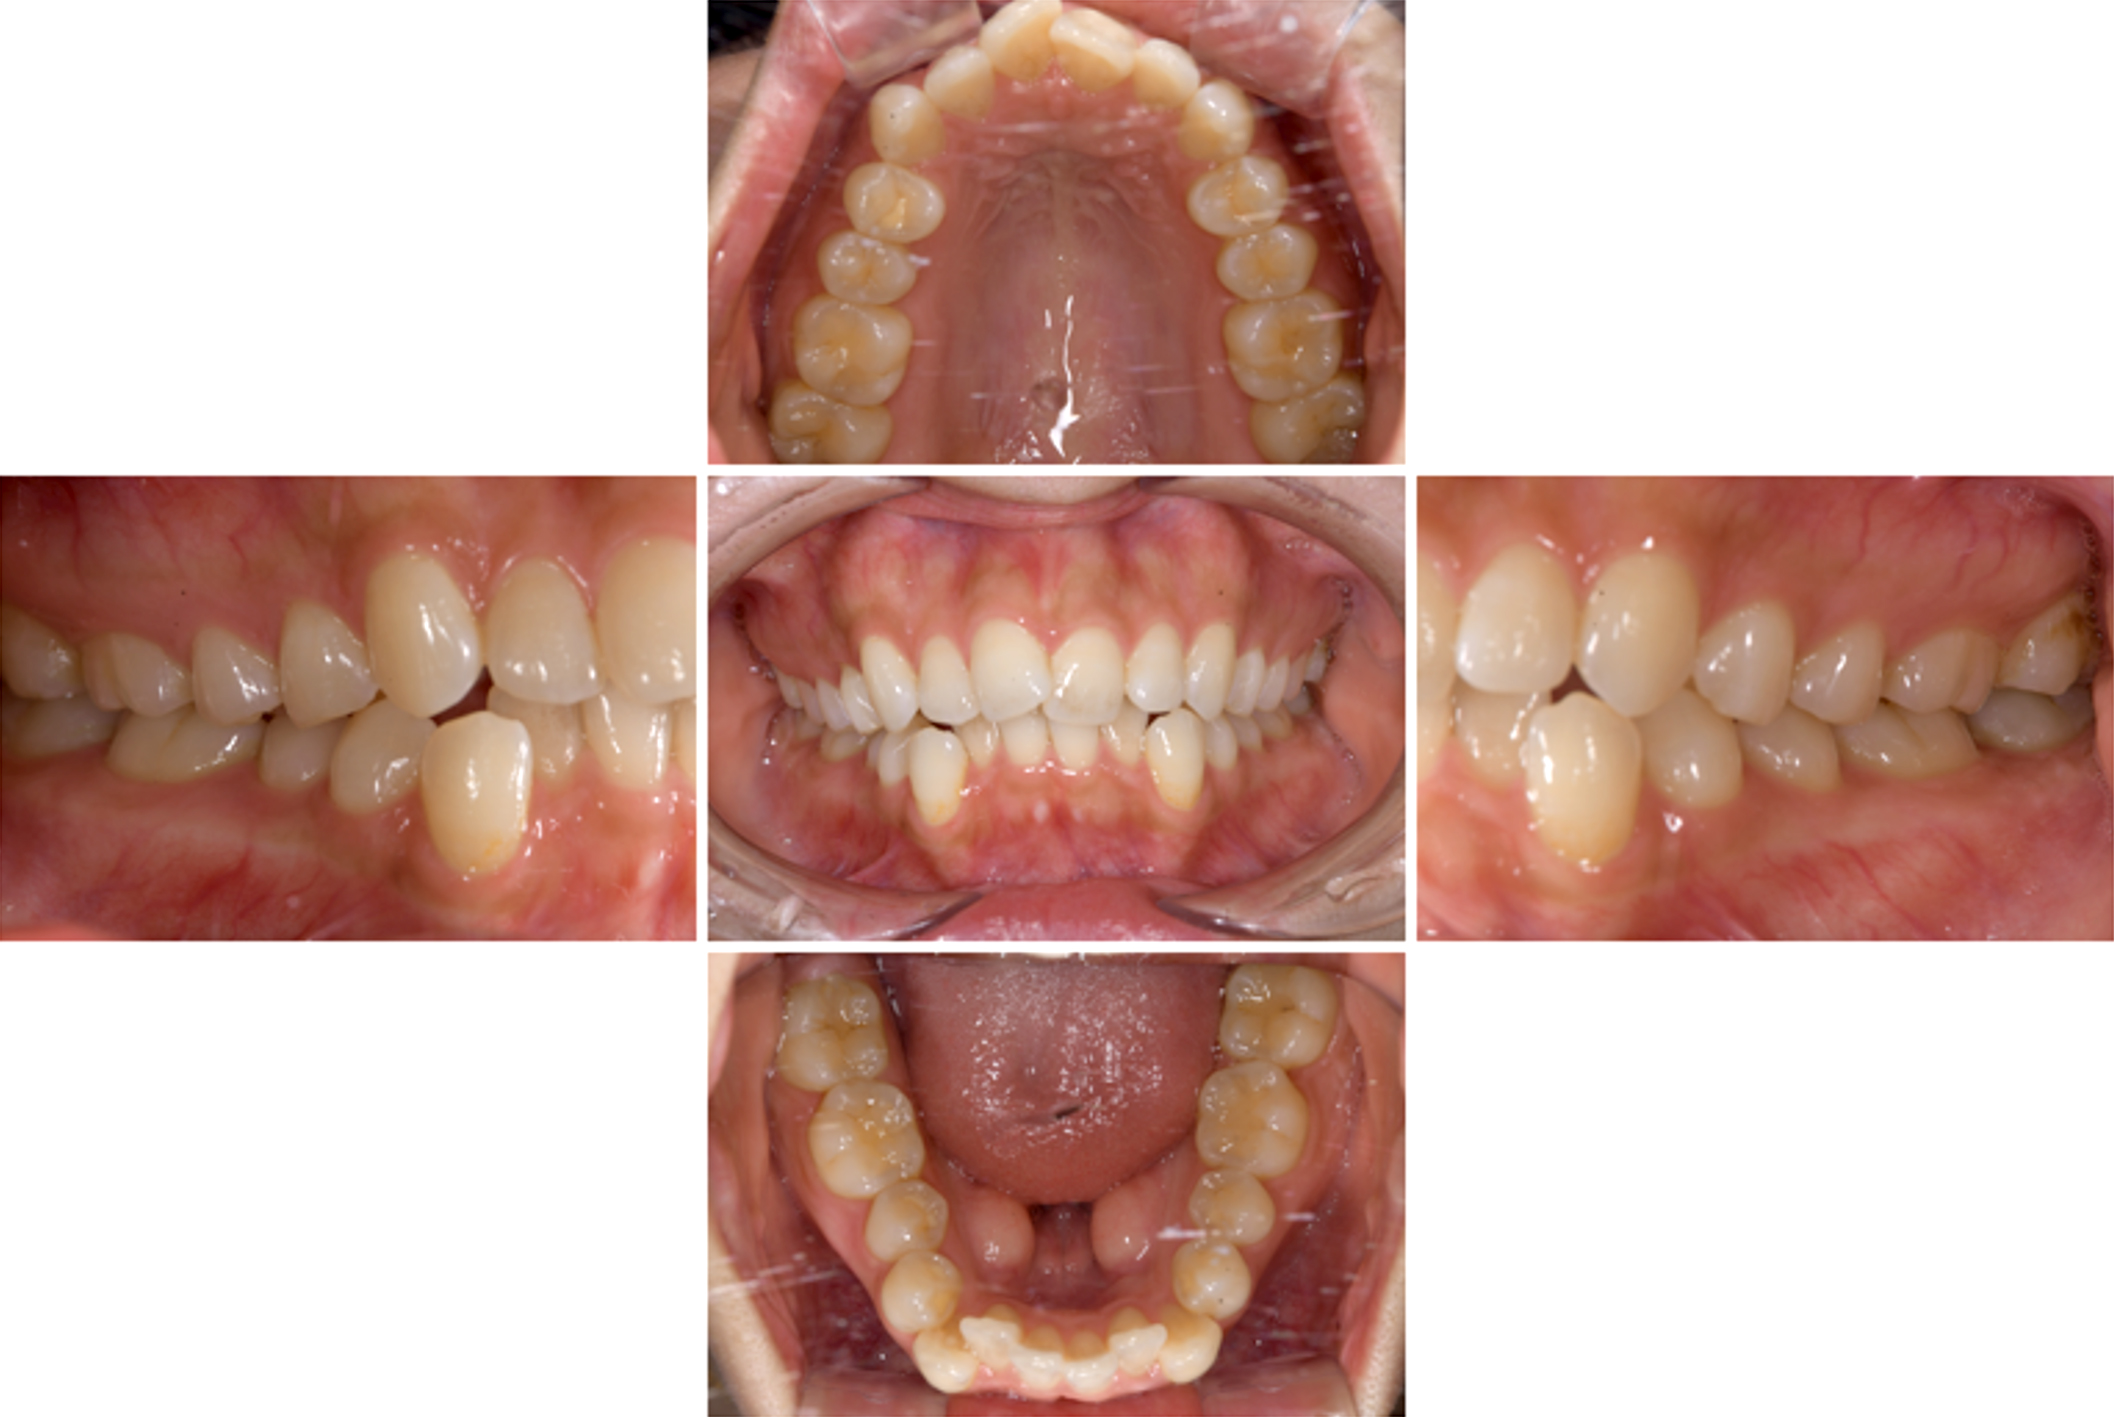

| 主訴 | 歯並びを治したい |

|---|---|

| 治療期間 | 5か月 |

| 治療費 | 部分マウスピース矯正(モニターキャンペーン)と ホワイトニングセット 422,596円(税込) |

| 治療内容 | 目立ちにくいマウスピース矯正 (非抜歯矯正) 歯と歯の間に隙間をつくることにより、歯列弓を広げながら治療を行いました。 また矯正用マウスピースをトレー代わりにし、ジェルを入れてホームホワイトニングを同時に行っております。 |

| 治療のリスク | ・後戻りする可能性があるのでリテーナーを最低でも矯正期間以上はつける必要があります。 ・ホワイトニング後、一時的に痛みが出る場合があります。 |